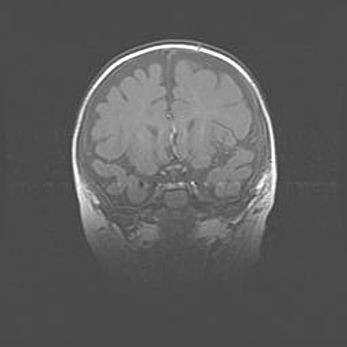

Лейкомаляция с кистозно-глиозной дегенерацией головного мозга.

Возраст: 2 месяца 25 дней

Вес: 6400 г

Окружность головы: 40 см

Срок гестации: 41 неделя

Лейкомаляцию относят к ишемически-гипоксическим повреждениям головного мозга, диагностируемым у новорожденных. При лейкомаляции в головном мозге обнаруживают очаги некроза, возникшие после тяжелой гипоксии и нарушения кровотока. В процессе морфогенеза очаги проходят три стадии: 1) развития некроза, 2) резорбции и 3) формирования глиозного рубца или кисты. Перивентрикулярная лейкомаляция (ПЛ) встречается примерно в 12% случаев среди новорожденных, обычно – у недоношенных детей, причем, частота ее зависит от массы, с которой младенец появился на свет. Наибольшее число малышей страдает лейкомаляцией, если масса при рождении 1500-2500 г.